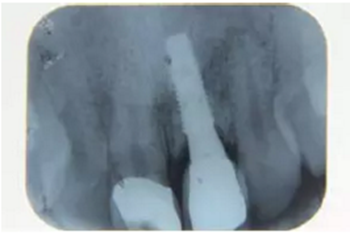

種植完成后可以通過拍攝曲面體層或是根尖片來確認(rèn)種植體的植入情況,并作為資料加以保存。

種植手術(shù)完成2周后進(jìn)行拆線??梢钥闯鲕浗M織愈合良好。

圖7 曲面體層片